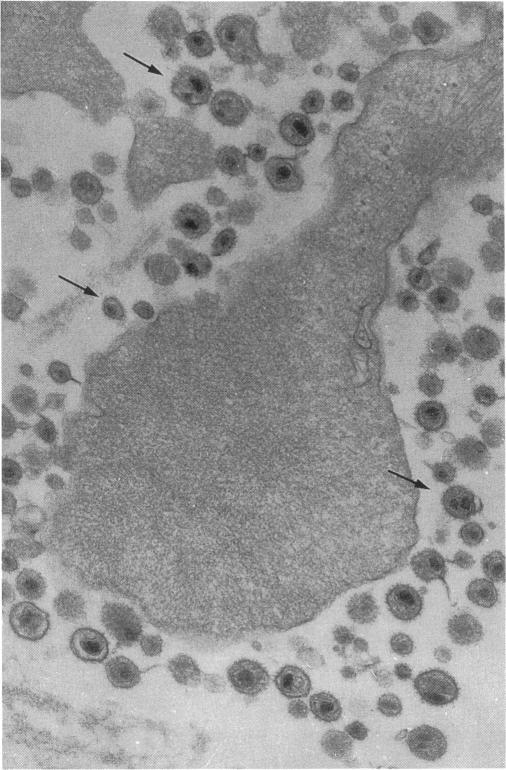

绵羊梅迪-维斯纳病毒诱导的间质性肺病中淋巴细胞性肺泡炎的特征

Characterization of the lymphocytic alveolitis in visna-maedi virus-induced interstitial lung disease of sheep.

In order to investigate the contribution of lymphocytes to interstitial lung disease in animals with visna-maedi infection, we studied in parallel bronchoalveolar cells and lung tissue from slaughter-house animals (n = 29) and from colostrum-deprived lambs transtracheally inoculated with field isolates of visna-maedi virus (n = 9) or saline (n = 6). Lymphocyte subpopulations were identified in bronchoalveolar lavage by immunofluorescence and flow cytometry analysis and in lung tissue using indirect immunohistochemistry. In infected animals a lymphocytic alveolitis containing CD4 and CD8 lymphocytes was observed. Peribronchovascular lymphoid nodules comprise mostly CD4 lymphocytes. Alveolar lymphocytes of both subsets displayed increased expression of MHC class II antigens in animals with naturally occurring maedi but not in experimentally infected ones. A sequential process of lymphocyte attraction and activation is likely to occur in vivo as part of the alveolitis.

为了研究淋巴细胞在维斯纳-梅迪病毒感染动物的间质性肺病中的作用,我们同时研究了来自屠宰场动物(n = 29)以及经气管接种维斯纳-梅迪病毒野毒株(n = 9)或生理盐水(n = 6)的初乳缺乏羔羊的支气管肺泡细胞和肺组织。通过免疫荧光和流式细胞术分析在支气管肺泡灌洗中鉴定淋巴细胞亚群,并使用间接免疫组织化学在肺组织中进行鉴定。在感染动物中观察到含有CD4和CD8淋巴细胞的淋巴细胞性肺泡炎。支气管血管周围淋巴结节主要由CD4淋巴细胞组成。在自然发生梅迪病的动物中,两个亚群的肺泡淋巴细胞均显示MHC II类抗原表达增加,但在实验感染的动物中未观察到这种情况。作为肺泡炎的一部分,体内可能会发生淋巴细胞吸引和激活的连续过程。

An electron microscope study of tissue cultures infected with visna virus.对感染维斯纳病毒的组织培养物进行的电子显微镜研究。

Virology. 1961 Aug;14:463-75. doi: 10.1016/0042-6822(61)90339-7.